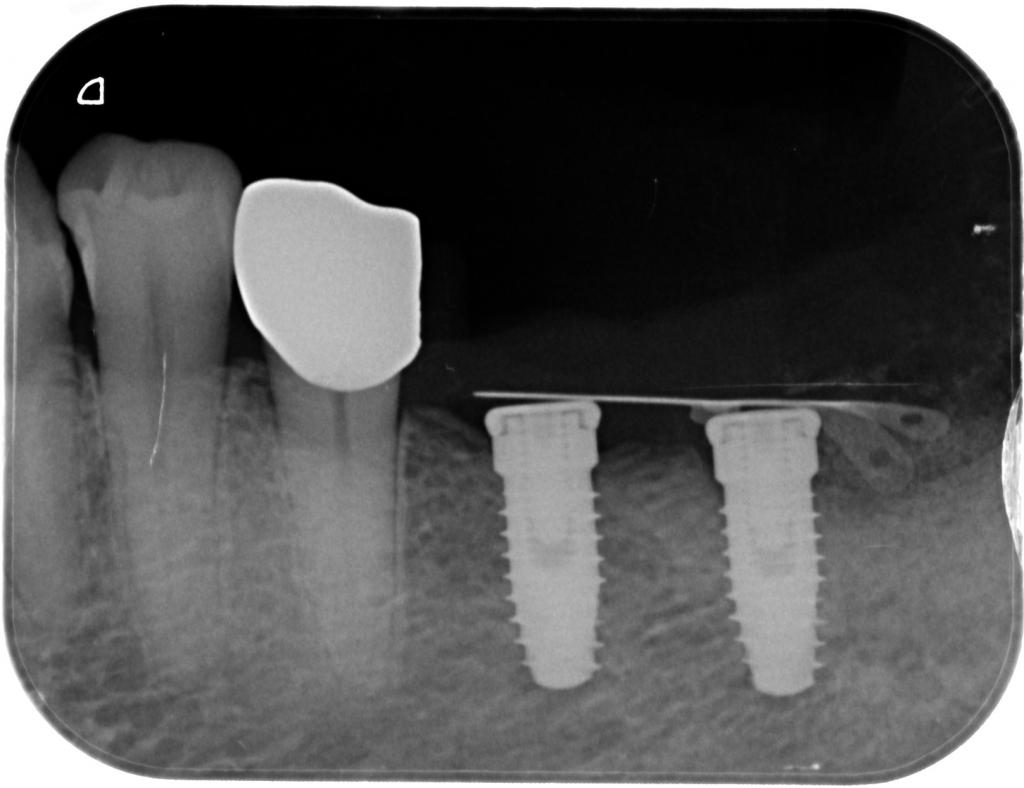

- GBRを併用してインプラントを埋入した時のレントゲン写真です。

この状態で、骨を造成した部が石灰化するのを待ちます。